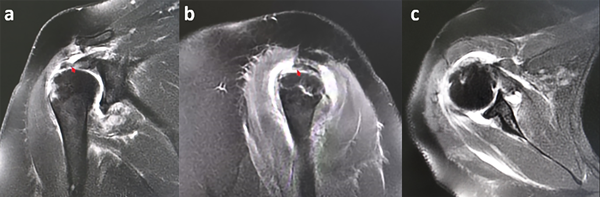

Más tarde, la paciente acude a interconsulta con nuestro equipo, se aplica el protocolo A.R.A.R.A.I.10 y se comprueba clínicamente anestesia de la cara lateral del brazo afectado, dermatoma correspondiente al nervio axilar o circunflejo (no diagnosticada previamente) confirmado posteriormente con electromiografía concluyente como neuropraxia del nervio axilar. Mediante resonancia magnética simple se detectaron lesiones concomitantes de hombro derecho y se evidenció: avulsión del supraespinoso e infraespinoso con fragmento óseo perteneciente a la tuberosidad mayor, compatible con el diagnóstico de tríada terrible del hombro (fig. 3).

Figura 3: RM en la que se observa avulsión del supraespinoso e infraespinoso con fragmento óseo perteneciente a la tuberosidad mayor. A) Corte coronal en T2. B) Corte sagital en T2. C) Corte axial en T2.